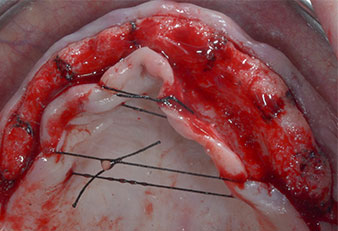

Поради сравнително твърдата кост (D2) в тази област, 10-милиметровото имплантно ложе в позиции 11 и 21 беше завършено с ротационен дрил с диаметър 4 mm в комбинация с W&H хирургичен обратен наконечник WS-75 L, W&H имплантологичен мотор Implantmed и опционалния W&H Osstell ISQ модул. За разлика от това, благодарение на меката кост, дисталните зони се подготвят до окончателен диаметър 3 mm, използвайки накрайник за Piezomed I3P. Имплантите най-накрая са поставени трансгингивално, за да остеоинтегрират за три месеца (Фиг. 6-10). Съществуващата протеза се фиксира на четирите временни импланта (Фиг. 8).